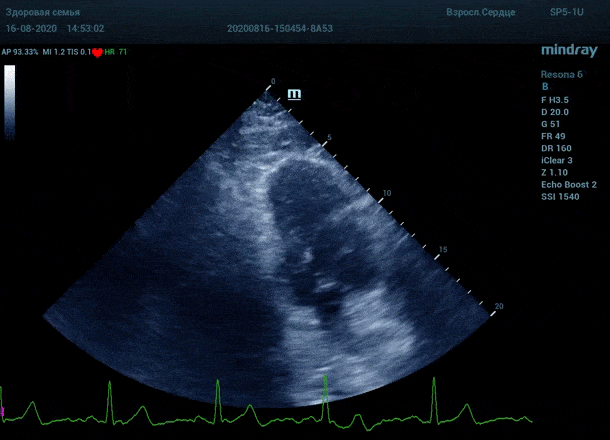

Обзор функции УЗИ: адаптивный колорайзинг

Глаз каждого человека по своей природе уникален. Одни люди лучше видят белый и серый цвет, прекрасно различают все его оттенки. Другим людям проще ориентироваться в голубом, синем и фиолетовом диапазоне, холодных тонах изображения. Однако большинство прекрасно видит оранжевый цвет, и очень четко отличает его от черного – анэхогенного пространства.

Адаптивный колорайзинг - настоящая находка для опытного врача ультразвуковой и функциональной диагностики. Для тренированного глаза открывается новый мир четких контуров, совершенно другой взгляд на привычные структуры сердца.

Данная функция присутствует в большинстве моделей Mindray, с возможностью эхокардиографического исследования. Ограниченное ЭХО окно можно победить разными путями.